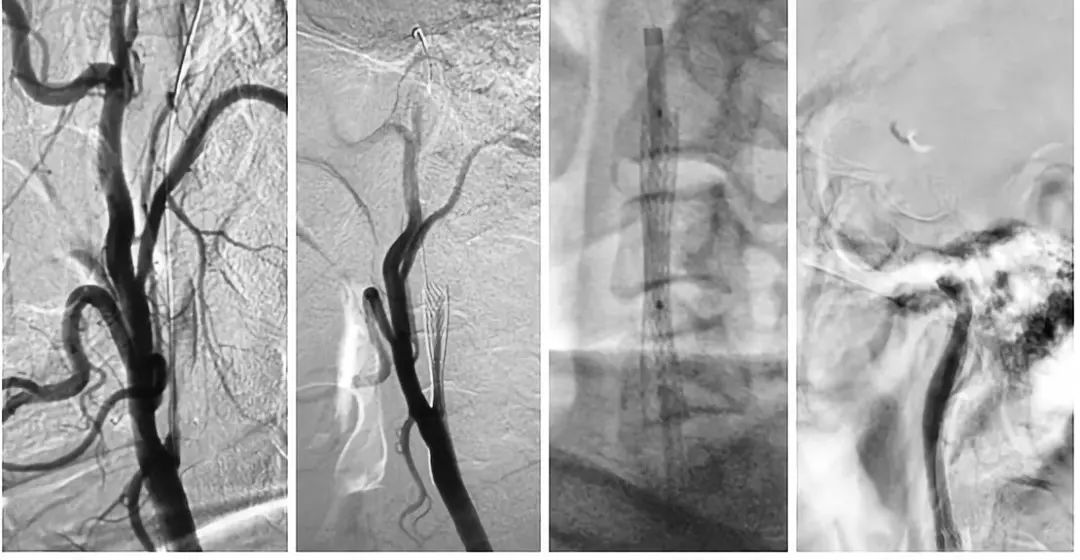

DSA结果提示:左侧颈内动脉次全闭塞,远端未见显影,左侧大脑中动脉闭塞,前交通动脉开放,左侧椎动脉起始部重度狭窄(图3-5)。

图3

图4

图5

局麻下,将8F导引导管上行至颈总动脉远端,在路径途指导下,将微导丝(Transcend)、微导管(Echelon-10)通过颈内动脉狭窄段至C2段,造影证实微导管位于真腔内,颈内动脉末端闭塞,交换出微导管,沿导丝送入Maverick(2.0x20mm)球囊至狭窄处,予以扩张球囊,造影提示狭窄有所改善,导引导管上行困难,遂沿导丝送入Wallstent(9x30mm)支架至狭窄处,释放支架,造影提示残余狭窄率约为60%,遂沿导丝送入LitePAC (4.0x30mm)球囊至狭窄处予以后扩张,造影提示狭窄明显改善,将球囊半充盈状态,导引导管沿球囊越过支架支颈内动脉C1段远端,再次造影示颈内动脉末端仍然闭塞,(图6)

图6